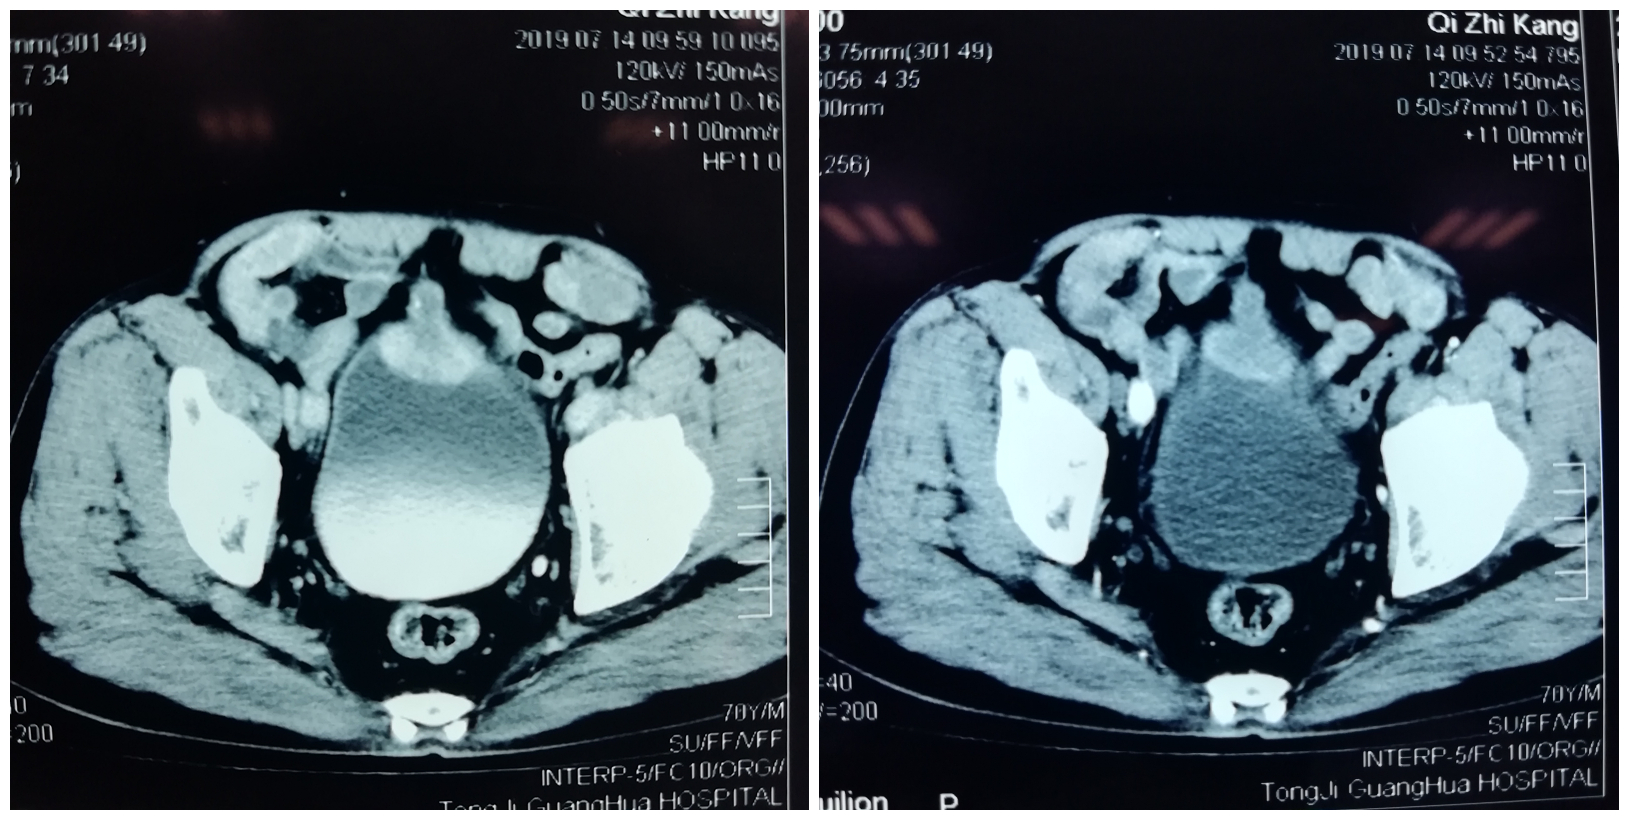

患者为男性,70岁,主诉1月余前无明显诱因出现肉眼血尿,呈间断性发作,无明显畏寒发热,无明显疼痛不适,就诊于当地医院,行增强CT检查提示“膀胱前上壁改变,考虑脐尿管癌,累及膀胱”,建议患者积极手术治疗。现为求手术治疗,就诊于我院泌尿外科门诊,门诊拟“脐尿管恶性肿瘤”收入泌尿外科病房。患者自发病以来,精神、食欲及睡眠一般,大便正常,体重未见明显减轻。

患者术前CT